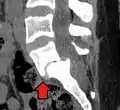

Anterolisthesis L5/S1

Anterolisthesis L5/S1. Blue arrow normal pars interarticularis. Red arrow is a break in pars interarticularis.

Magnetic Resonance Imaging (MRI)

Magnetic resonance imaging is the preferred advanced imaging technique for evaluation of spondylolisthesis.[30] Preference is due to effectiveness, lack of radiation exposure, and ability to evaluate for soft tissue abnormalities and spinal canal involvement.[30][31] MRI is limited in its ability to evaluate fractures in great detail, compared to other advanced imaging modalities.[32]